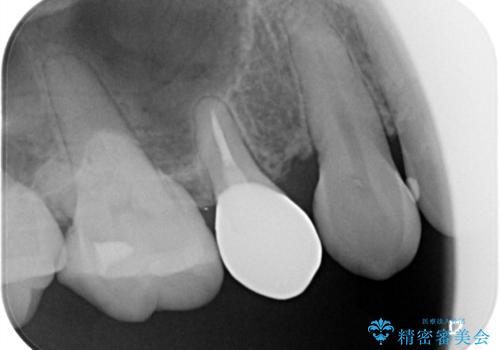

物が詰まりやすく歯茎が腫れる

- 元々入っていたセラミックインレーは、6番目と7番目の歯の隙間を無理やり咬合面の近遠心的幅径を伸ばし埋めたような形態で、下部鼓形空隙が広めで食渣が溜まりやすい状態でした。

セラミックインレーを除去したところ、残存歯質が少なく破折のリスクを説明し、オールセラミッククラウン(スタンダード)でのやり替えとなりました。

オールセラミッククラウンの膨隆で下部鼓形空隙を適切な大きさに調整しました。